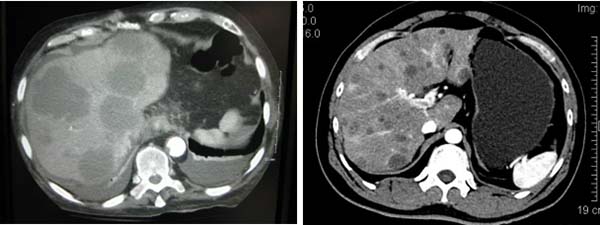

多发肝转移癌CT影像